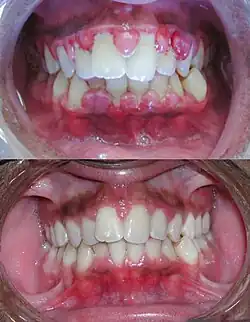

Beim Zahnfleischbluten reagiert das Zahnfleisch auf Berührungen verschiedenster Art, z. B. Zahnreinigung mit Bürste oder Zahnseide, mit Bluten. Ist die Ursache entzündlich bedingt, so ist die Gingiva (Zahnfleisch) dabei mehr oder weniger stark angeschwollen und rot verfärbt. Rötung und Schwellung des Gewebes beruhen auf Erweiterungen der Blutgefäße. Die Durchblutung ist verstärkt und die Gefäßwände werden durchlässig. Dadurch tritt Blutplasma in das benachbarte Gewebe aus, das Zahnfleisch schwillt an. Zuerst schwellen die Zahnfleischpapillen zwischen den Zähnen, nachfolgend in den übrigen Bereichen an. im Gegensatz dazu ist eine gesunde Gingiva blass rosafarben. Blutet eine blasse, nicht geschwollene Gingiva, so ist die Ursache nicht entzündlich bedingt, sondern beruht auf anderen Gründen.[1]